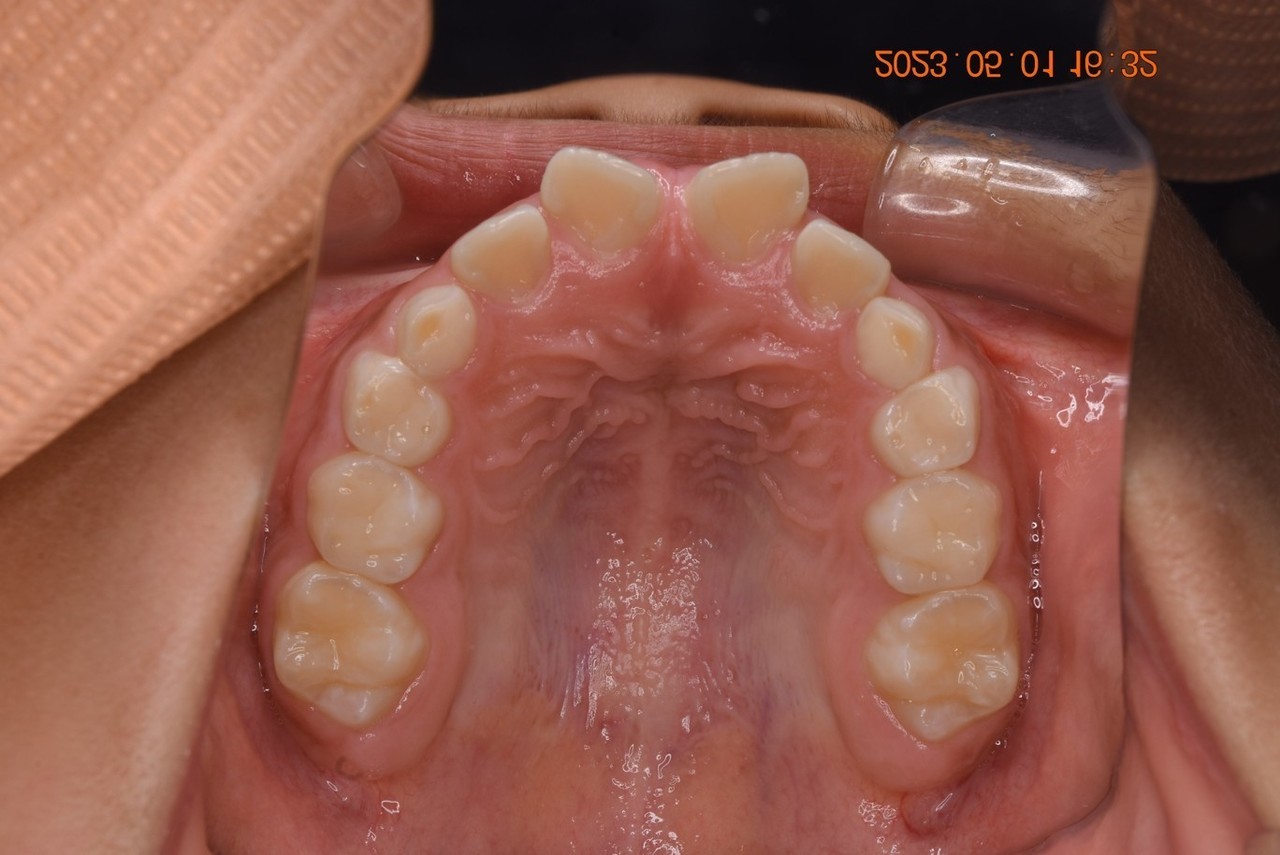

03:2番目の歯が奥に生えていた方

1期矯正治療の症例写真

1期矯正治療終了後の症例写真

第2大臼歯萌出完了

• 主訴:前から2番目の歯が後ろ側に生えている

• 診断あるいは主な症状:叢生

• 年齢:10歳(治療開始年齢)

• 治療に用いた主な装置:マルチブラケットによる歯列矯正(小児矯正)

• 抜歯部位:なし

• 治療期間:2年8ヶ月

• 治療回数:37回(矯正治療を目的とした来院)

• 治療費概算:508,000円(税込)